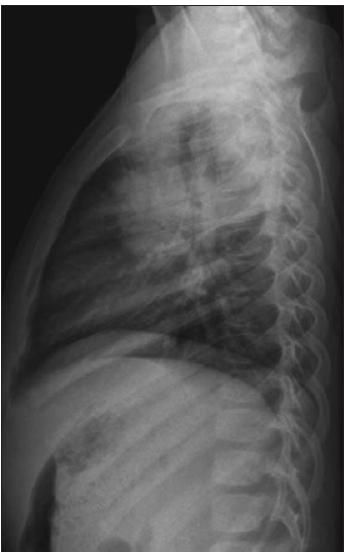

What are the findings in the upper abdomen? (D is the correct choice.)

Whether the CT scan was absolutely necessary in this patient's case is open to debate; however, this is in fact how the saga unfolded. Indeed, in the right suprarenal fossa are dystrophic, benign-appearing calcifications scattered throughout the right adrenal gland, which is of normal contour and size. There were no renal or liver calcifications, nor were there any rib fractures. It would be unwise to rely on a CT scan to show gallstones, if they were present. CT is notoriously misleading in this regard. Because gallstones vary in composition and density, they may be present but completely inapparent on CT scans. However, we had already eliminated this possibility on the sonogram.

4. Do the findings on the CT scan explain the patient's symptoms, now described as "pain on the entire right side of her body"? (B is the correct choice.) No.